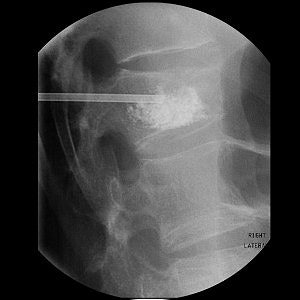

Eighty-year-old man with renal cell carcinoma who presented with lower back pain. Control CT scan (below) acquired immediately after vetebroplasty shows homogenous cement distribution in tumor necrosis with small ventral leakage. Control radiography (above) acquired three months after procedure shows stable vertebral body with unchanged location of cement filling. Schaefer O, Lohrmann C, Markmiller M, Uhrmeister P, Langer M, "Combined Treatment of a Spinal Metastasis with Radiofrequency Ablation and Vertebroplasty," (AJR 2003, Vol.180, pp.1075-1077).